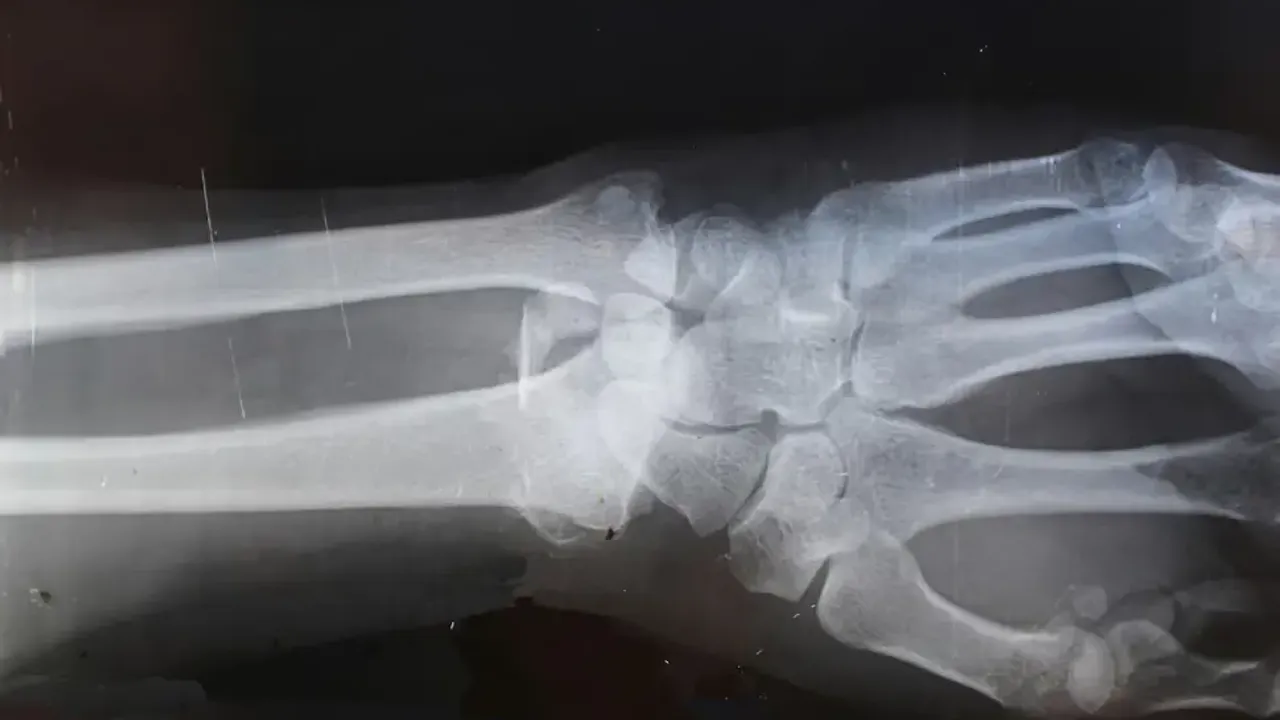

Çin menşeili ChoSun Daily'nin haberine göre bir deneme vakasında, bilek kırığı olan bir hastaya sadece 3 cm’lik bir kesiden bir enjeksiyon yapıldı ve yalnızca üç dakikada iyileşme sağlandı. Bu yapıştırıcı olmasaydı, bileği onarmak için metal plaka ve vidaların gerekeceği bir ameliyat yapılacak ve ayrıca bir yıl sonra bunları çıkarmak için ikinci bir ameliyat daha olacaktı. Enjeksiyondan üç ay sonra yapılan takip muayenesinde hastanın kırığının komplikasyonsuz olarak tamamen iyileştiği bildirildi.